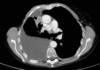

TC ventana pulmonar

Se ven mejor la vía aérea, vasos pulmonares y cisuras, pero todas las estructuras mediastínicas aparecen de un tono gris demasiado similar.